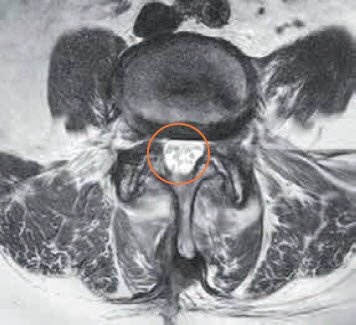

Abb. 3 – 4 zeigen MRI-Bilder nach der Dekompressionsoperation. Zwischen dem 4. und 5. Lendenwirbel (L4 / L5) ist weiterhin ein Wirbelgleiten ersichtlich, aber die Spinalstenose ist nicht mehr vorhanden (Pfeil). Durch die Operation konnte die Einengung auch auf Höhe L3 / L4 beseitigt werden.